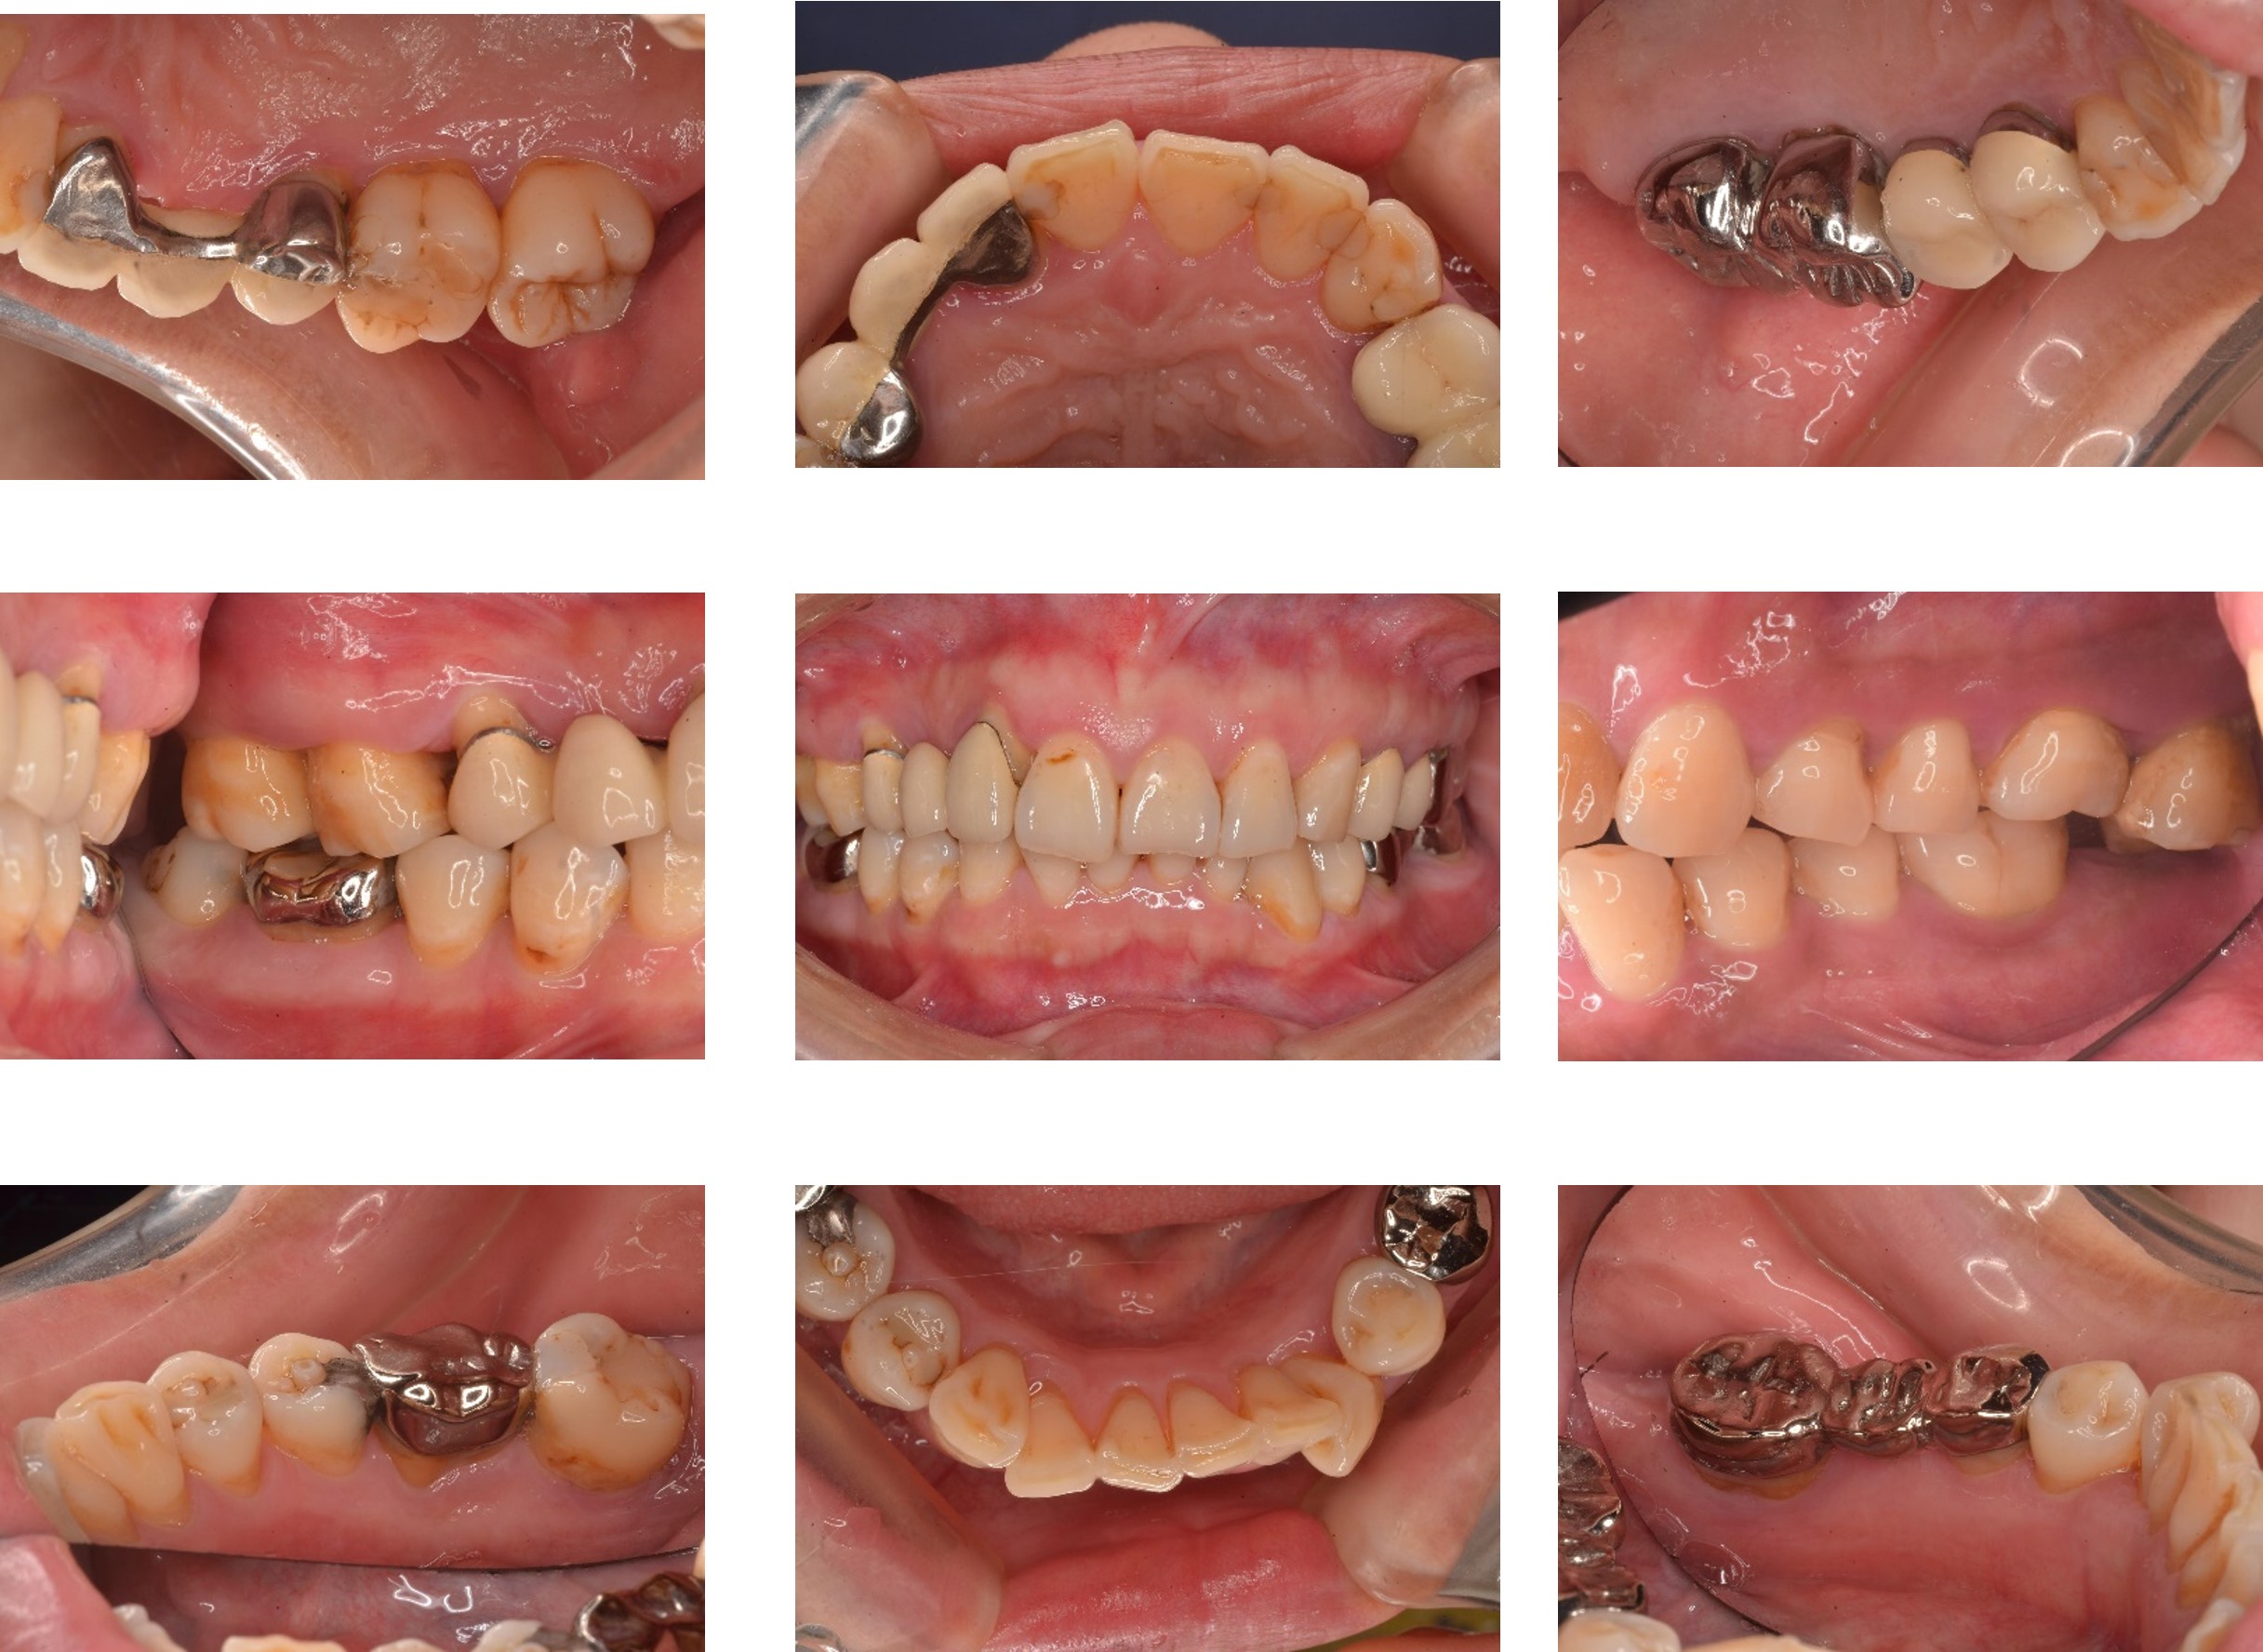

牙周檢查-相片

完整口腔檢查與紀錄:

醫師會進行全口檢查,記錄牙周囊袋深度、牙齦發炎程度、牙齒鬆動狀況等。

牙周囊袋深度探測:

使用牙周探針深入牙周囊袋,測量囊袋深度,評估牙周病嚴重程度與後續治療方向。